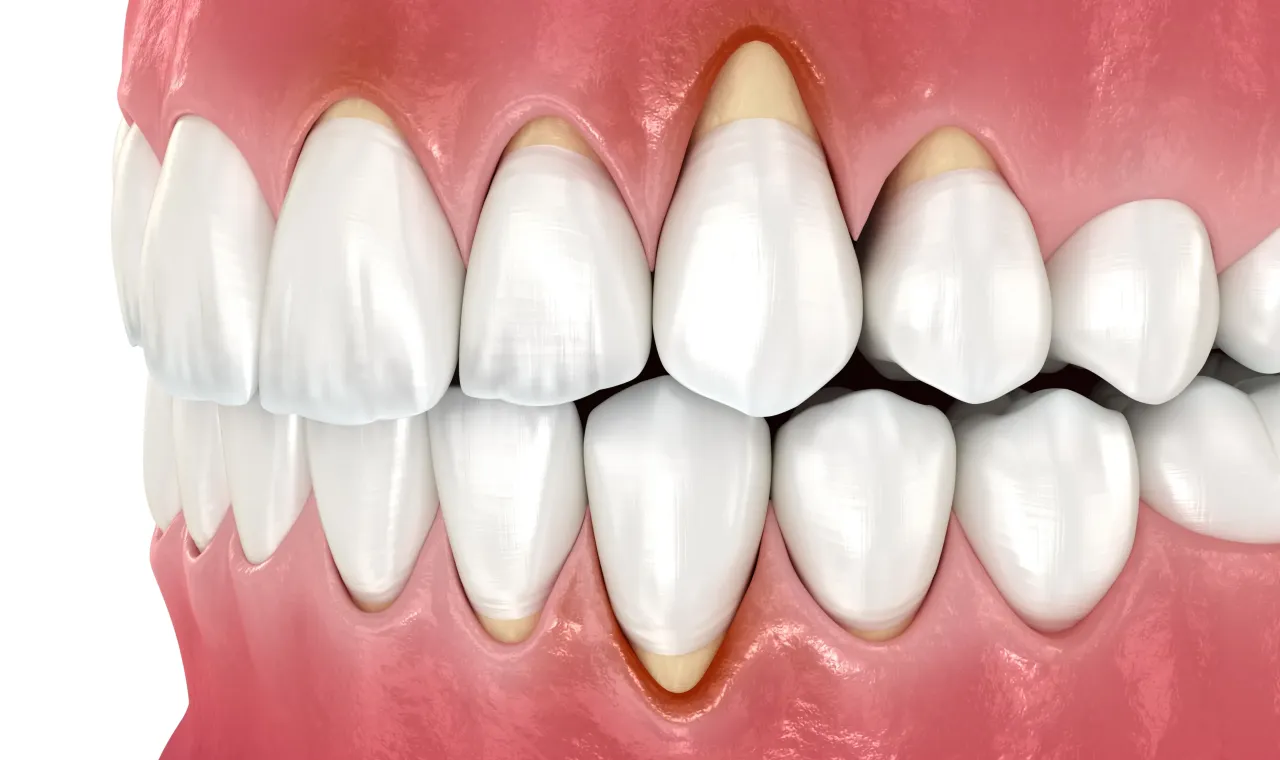

Zęby wydają się dłuższe: co wygląd dziąseł mówi o ich zdrowiu

Wizualne zmiany są często tym, co ostatecznie skłania pacjentów do wizyty u stomatologa. W przypadku recesji dziąseł zęby zaczynają optycznie wydawać się dłuższe niż dotychczas. Dzieje się tak, ponieważ obniżająca się linia dziąseł odsłania część korzenia, która normalnie jest ukryta. Możesz również zauważyć widoczne odsłonięcie żółtawej powierzchni korzenia zęba, która różni się kolorem od białej korony. Ta zmiana estetyczna jest bezpośrednim i niepokojącym skutkiem obniżenia linii dziąseł.

Recesja dziąseł to proces stopniowego obniżania się linii dziąseł, prowadzący do odsłonięcia szyjek i korzeni zębów. Jest to poważny problem, który wymaga uwagi, ponieważ nieleczony może prowadzić do szeregu komplikacji, od zwiększonej nadwrażliwości po utratę zębów.

Kiedy mówimy o recesji dziąseł, chodzi o to, że tkanka dziąsłowa, która normalnie chroni korzenie zębów, zaczyna się cofać. Odsłonięte korzenie zębów nie są chronione przez twarde szkliwo, tak jak korony. Zamiast tego pokrywa je zębina, która jest znacznie bardziej porowata i podatna na działanie kwasów oraz bakterii. To sprawia, że są one znacznie bardziej narażone na próchnicę korzenia i nadwrażliwość, a także na uszkodzenia mechaniczne.